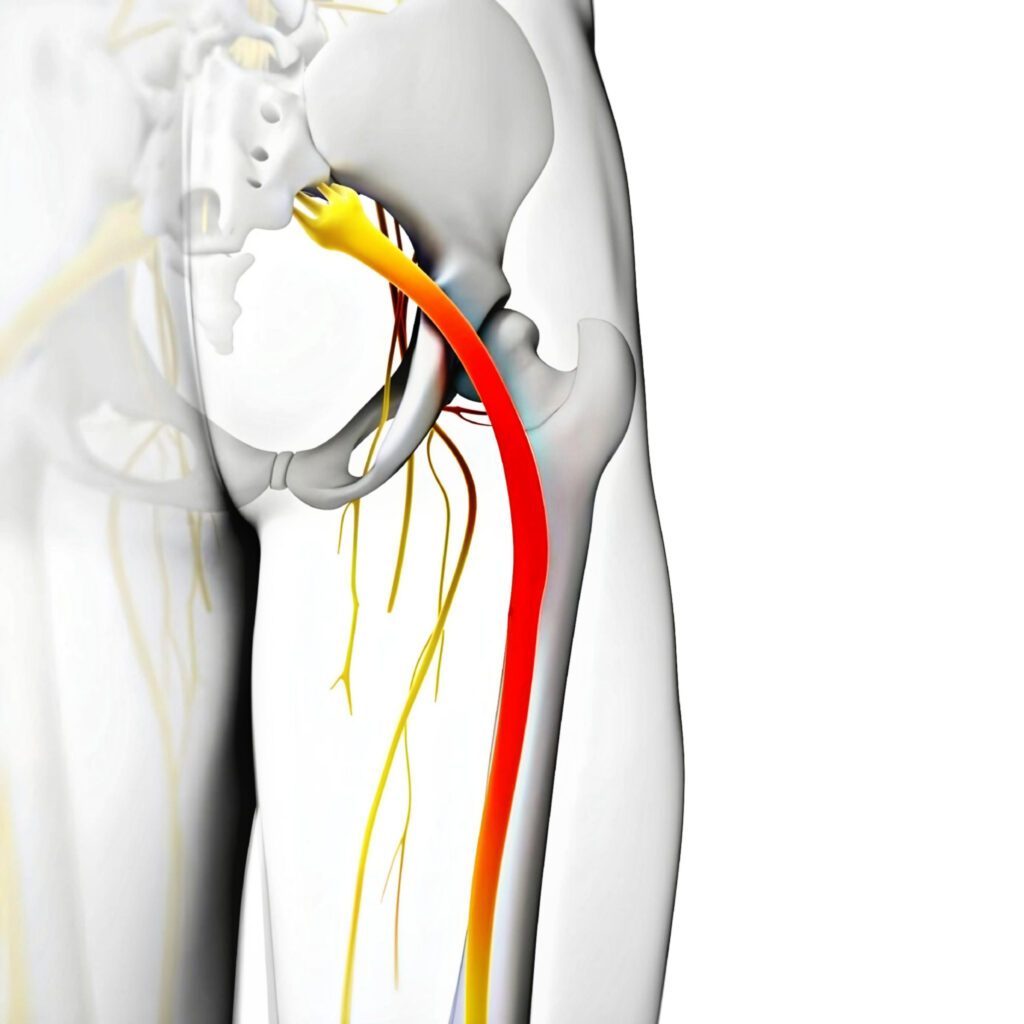

Sciatic pain is felt in the lower back, buttock, and sometimes in various parts of the leg or foot. As well as the pain which is sometimes severe, the leg may become numb or weak. It may become difficult to move or have control of the leg. Usually, the symptoms are just felt on one side of the body.

Sciatica is a collection of symptoms rather than a diagnosis for what is irritating the root of the nerve, causing the pain. This point is important to understand, because treatment for sciatic symptoms will differ, according to the underlying cause of the symptoms.